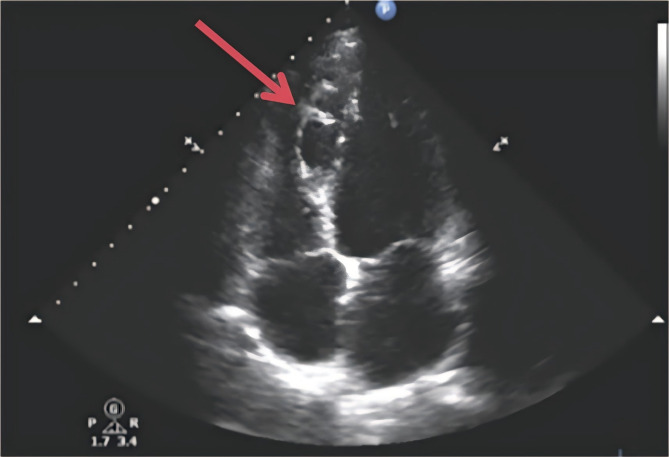

Background: Hypoparathyroidism (HypoPT) is a rare endocrine disease characterized by hypocalcemia, hyperphosphatemia, and insufficient or no parathyroid hormone (PTH) secretion. Hypoparathyroidism-induced chronic hypocalcemia may lead to cardiovascular complications, including myocardial dysfunction and arrhythmias. Interventricular septal dissecting aneurysm, a rare cardiac anomaly, typically arises following structural or ischemic heart disease. This disease can lead to ventricular septal rupture and aneurysmal cystic chamber formation, causing changes in cardiac structure and hemodynamics as well as giving rise to various heart complications.

Case presentation: No study has reported an association between hypocalcemia and cardiac masses. We encountered a case of hypoparathyroidism in a middle-aged woman who developed an interventricular septal dissecting aneurysm. Upon examination, we found that HypoPT has a profound impact on the heart.